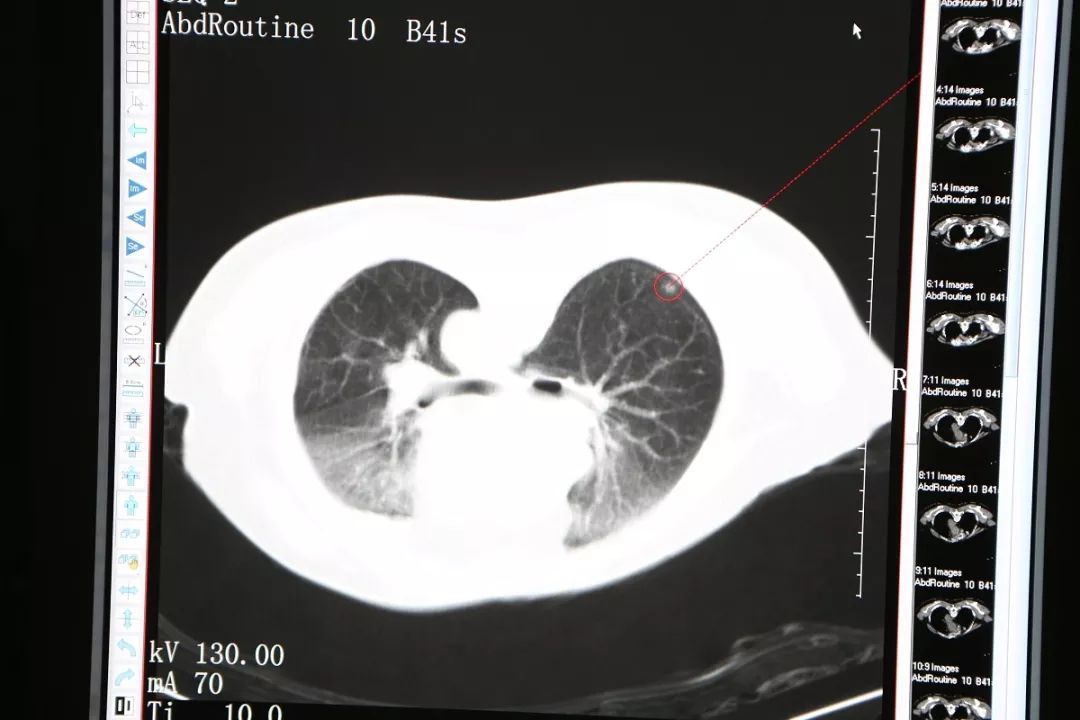

今年69岁的穆阿姨自退休以后就跟着儿子生活在新西兰,并取得了当地绿卡,偶尔返回厦门居住。今年7月她独自返回厦门小住,电视上“双肺毛玻璃”几个字眼触动了她,原来她在今年3月份的体检表上也有这几个字,第二天她去复查胸部CT显示“与2018-03-21CT比较:右肺下叶背段及左肺上叶磨玻璃结节较前相仿”,这时候她体内的磨玻璃影没有变化,她长舒了一口气,但医生建议她继续观察不要放松。到了10月份,她再次到当地医院做CT,发现磨玻璃影虽然没有变大,但是密度增加了,这时候她想起了在电视节目中看到的信息:“密度增加”就要引起注意,如今“密度增加”了表明病症在讯速进展。

肺部磨玻璃样结节是指原发于肺部的均匀含气结节。病灶会沿肺泡生长,并不破坏肺泡构架。但它的密度比正常的肺部组织高,CT影像上面表现为磨玻璃影。典型的磨玻璃样结节多数是癌前病变或者早期肺癌。

11月26日,穆阿姨被送至微创治疗室在CT引导静脉全麻下行右肺结节氩氦刀冷冻消融术,在实施静脉全麻后,术者将她摆成俯卧位,CT扫描以右肺背段近胸膜处结节为靶区,在CT引导下,用氩气超冷刀经穿刺点准确的穿刺到右肺结节,然后开始实施冷冻。术中通过CT扫描监测冷冻范围和有无并发症的发生,经过两个5分钟的冷冻循环后,CT扫描显示右肺的结节被成功的消融了。CT扫描见冰球覆盖靶区,复温后拔除超冷刀,包扎穿刺点,术中出血2ml,无手术标本,术后麻醉清醒,未诉不适,生命体征平稳。